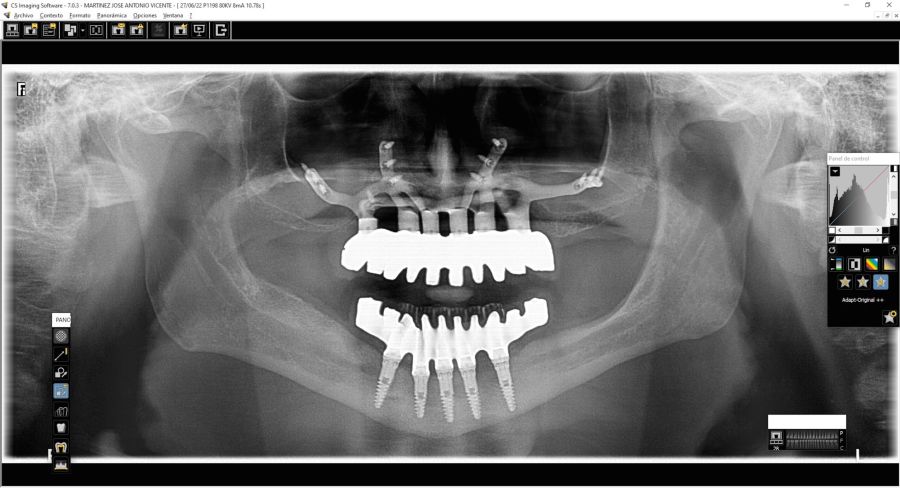

We present the clinical case of a 65-year-old patient with an implant-supported dentoalveolar rehabilitation on implants in the upper arch, placed in 2010, on which he referred pain, mobility and suppuration. After an orthopantomography, we observed a severe generalised perimplantitis in the upper arch, affecting all implants (Figure 1). It was explained to the patient that it was not possible to perform a bone regeneration of the lost tissues.